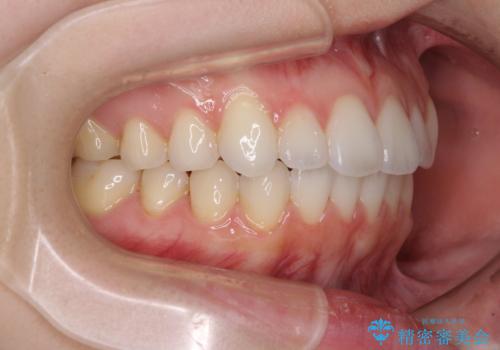

- 矯正治療の後戻りを気にして来院された患者様です。

後戻りは軽微でしたが、舌突出癖が認められ、初診時には上下前歯に舌がはまるスペースができていました。

舌突出癖の改善を行いながら、インビザライン・ライトにより矯正治療を行うこととしました。

舌突出癖の改善により上下前歯が接触するようになり、前歯でものを咬みきる必要のある食事がスムーズに行えるようになりました。